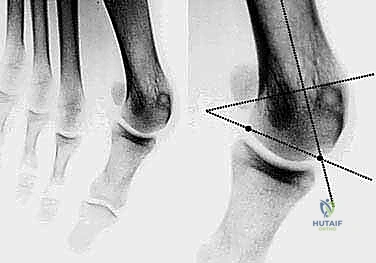

- التصوير بالأشعة السينية الدقيقة (Weight-Bearing X-Rays): وهي خطوة حاسمة. يجب أن تؤخذ الأشعة والمريض واقف (يحمل وزنه على قدمه) لإظهار الحجم الحقيقي للتشوه.

- القياسات الهندسية لزوايا القدم: يقوم الدكتور هطيف بقياس زوايا محددة لتحديد نوع الجراحة، أهمها:

- HVA (Hallux Valgus Angle): زاوية انحراف الإبهام (الطبيعي أقل من 15 درجة).

- IMA (Intermetatarsal Angle): الزاوية بين العظمة المشطية الأولى والثانية (الطبيعي أقل من 9 درجات).

- DMAA (Distal Metatarsal Articular Angle): زاوية سطح المفصل، وهي الزاوية الأهم التي تحدد الحاجة لتقنية "ش